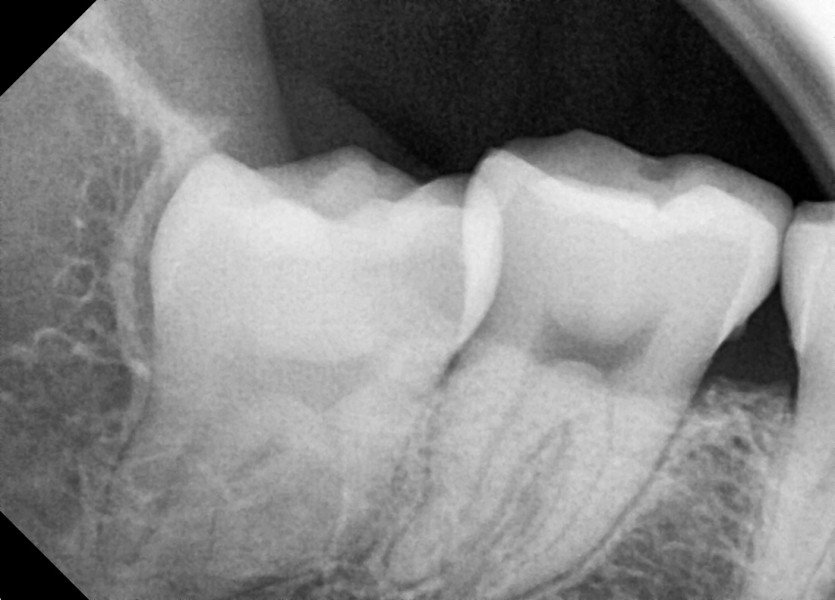

#28,38,48 사랑니 발치

구강 외과 전문의가 당일 발치했습니다.